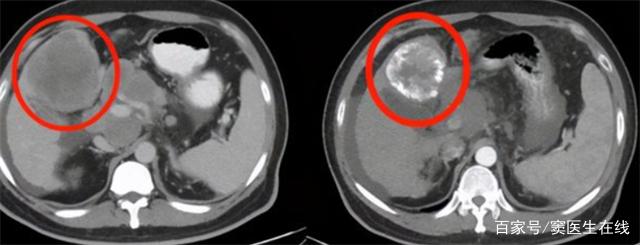

患者體溫37.8℃、血壓125/90、身高183cm、體重75kg。患者腹部壓痛、反跳痛明顯,腹部彩超檢查結果顯示肝臟存在多處病變,均為惡性,腹腔淋巴結腫大;癌胚抗原5.3 ng/ml;乙肝表面呈陽性。最終診斷為原發性肝癌晚期。